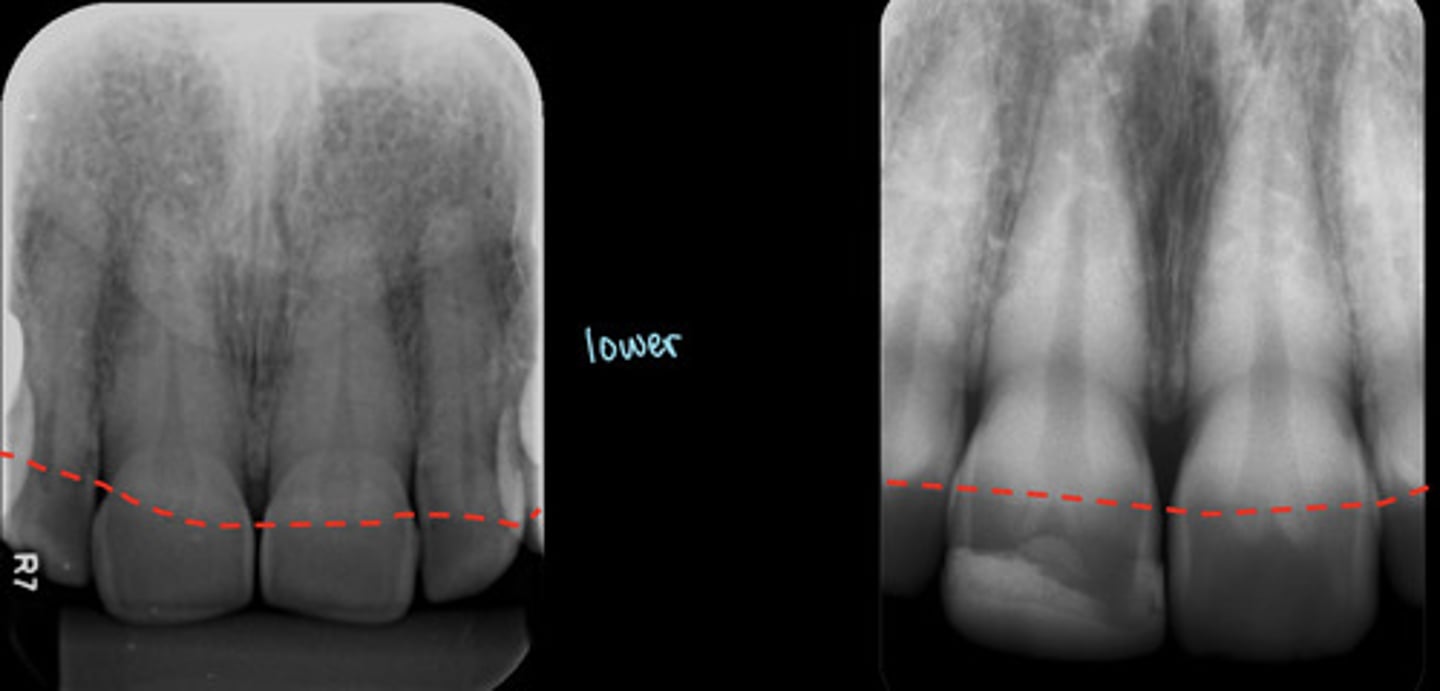

What are the dotted lines representing?

periodontal ligament space

Lamina dura